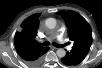

Perikarderguss

Akut auftretende perikardiale Flüssigkeitsansammlungen können ab ca. 250 ml zu einer Herzbeuteltamponade führen. Als Ursachen dafür kommen beispielsweise Aortendissektionen, perforierende Traumen, Urämie sowie bakterielle, virale und rheumatoide Perikardentzündungen in Frage. Computertomographisch lässt sich ein zirkulärer, dem subepikardialen Fettgewebe anliegender hypodenser Saum darstellen. Bei einer zugrunde liegenden Perikarditis können verdickte, kontrastmittelaufnehmende Perikardblätter nachweisbar sein.